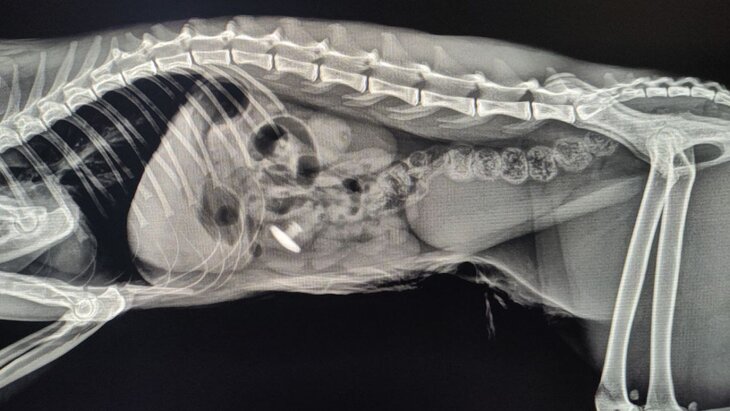

Фото: ГБУ "Мосветобъединение"

Заглушку для мебели, золотое украшение и даже провод обнаружили в желудках домашних животных специалисты ветклиник ГБУ "Мосветобъединение", рассказали Москве 24 в столичной госветслужбе.

Одним из спасенных стал кот Степа: он поступил в Бутовскую ветклинику с жалобами на рвоту после еды и слабость.

Хирург Дарья Матвеева провела коту операцию по извлечению инородного тела, после чего состояние животного сразу стабилизировалось, а заглушка была возвращена владельцам.